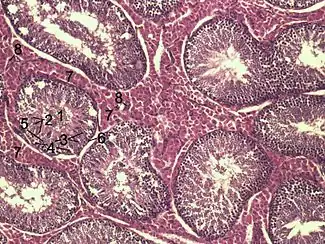

Histological section through testicular parenchyma of a boar. 1 Lumen of Tubulus seminiferus contortus, 2 spermatids, 3 spermatocytes, 4 spermatogonia, 5 Sertoli cell, 6 Myofibroblasts, 7 Leydig cells, 8 capillaries